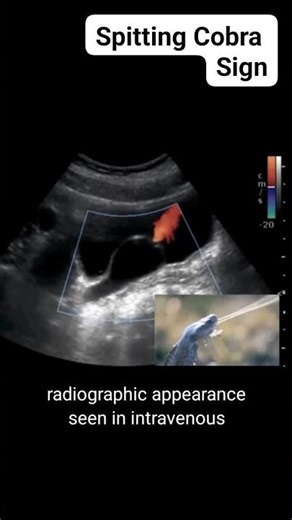

- IVP X-ray

X-ray - IVP X-ray

Time Protocol - IVP